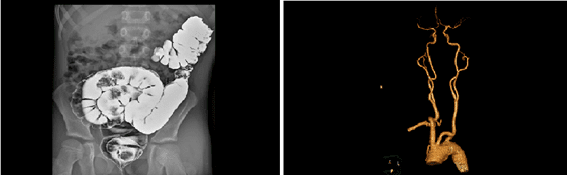

En los años 2000 aparecieron los primeros dispositivos de acceso vascular (DAV) compatibles con la alta presión, llamados en inglés CT rated por Computed Tomography. La Tomografía Computarizada (TC) consiste en la emisión de rayos X alrededor del paciente que generan imágenes de cortes transversales. Posteriormente estas imágenes están procesadas por un sistema informático, lo cual permite obtener imágenes en 3 dimensiones de los órganos y estructuras. En España la TC se conoce por las siglas TAC: Tomografía Axial Computarizada (o escáner).

Sin embargo, los catéteres CT rated no son solo compatibles con las inyecciones de alta presión en TAC ya que otras pruebas diagnósticas usan la alta presión: la resonancia y la angiografía.

Por esta razón, en inglés, los catéteres compatibles con alta presión se llaman también Power Injectable (que se podría traducir por compatible con la inyección “potente”/a presión), término que abarca todas las circunstancias en la cuales se usa alta presión.